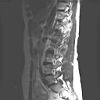

LWZ